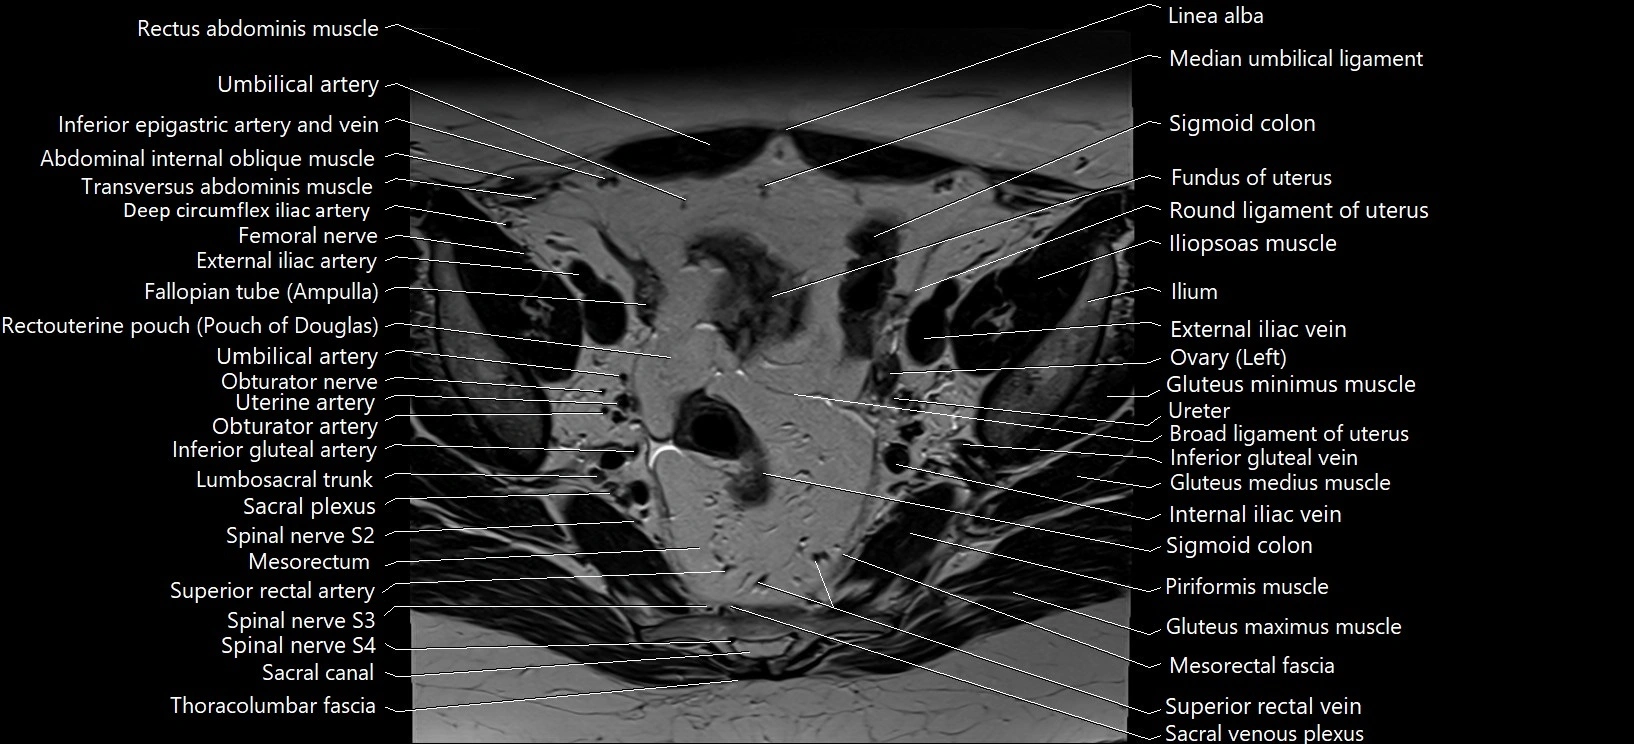

- Body of urinary bladder

- Body of uterus

- Broad ligament of uterus

- Common iliac vein

- External iliac artery

- External iliac vein

- Fundus of uterus

- Gluteus maximus muscle

- Gluteus medius muscle

- Gluteus minimus muscle

- Inferior gluteal artery

- Inferior gluteal vein

- Inferior mesenteric vein

- Internal iliac artery

- Internal iliac vein

- Left ovary

- Lumbosacral trunk

- Mesorectal fascia

- Mesorectum

- Piriformis muscle

- Rectouterine pouch (pouch of Douglas)

- Round ligament of uterus

- Sacral plexus

- Sigmoid colon

- Spinal nerve S2

- Spinal nerve S3

- Spinal nerve S4

- Superior rectal artery

- Superior rectal vein

- Umbilical artery

- Uterine artery

- Uterosacral ligament